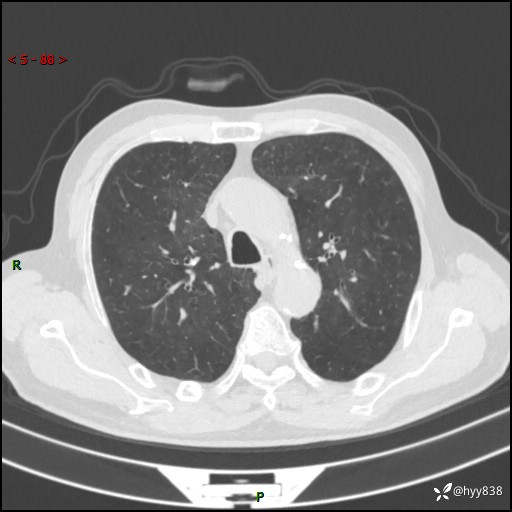

辅助检查:CT

胸部CT平扫